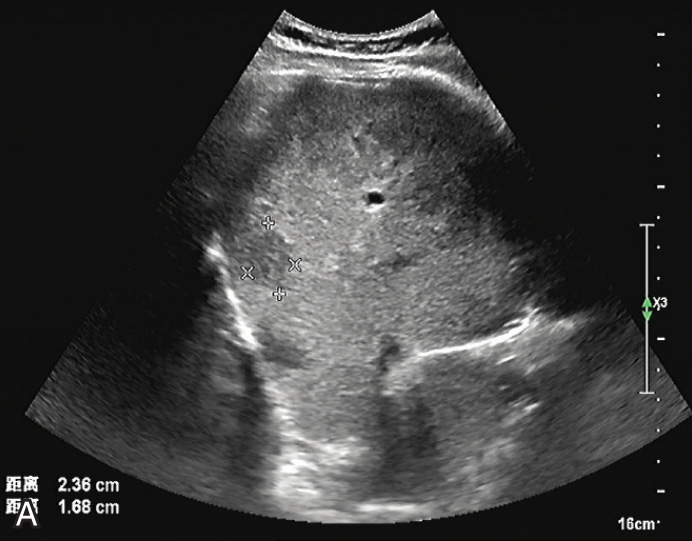

(2)回声特征:

较小的腺瘤为较均匀或不均匀的低或稍高回声,较大的腺瘤内常伴出血、坏死和液化,瘤体内出现不规则高回声、无回声区,构成混合回声结构(图1-5-1A)。